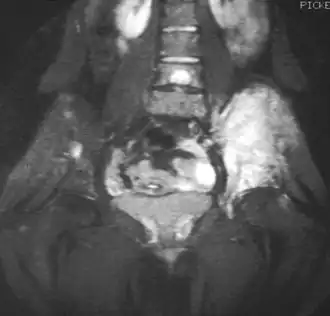

La resonancia magnética (IRM) podría ser usada rutinariamente en la investigación de los tumores malignos. La IRM mostrará la extensión total del tejido óseo y los tejidos blandos y establece la relación del tumor a las estructuras anatómicas cercanas (e.j. vasos sanguíneos).[14][15] Algunos investigadores sostienen que la IRM mejorada con contraste puede ayudar a determinar la cantidad de necrosis dentro del tumor, esto ayuda a determinar la respuesta al tratamiento antes de la cirugía.[15]

La TAC puede también ser usada para definir la extensión extraosea del tumor, especialmente en el cráneo, espina, costillas y pelvis. Tanto el TAC como la IRM pueden ser usados para el seguimiento a la respuesta del tumor a la radiación y/o quimioterapia.[14]